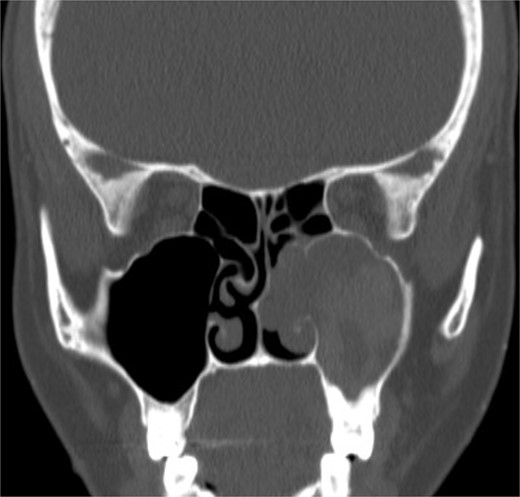

Isolated maxillary chronic invasive granulomatous fungal sinusitis

An 18-year-old adolescent mentally challenged male was complaining of chronic right thick purulent nasal discharge, cough, and headache, which did not respond to multiple courses of oral antibiotics. Purulent discharge was seen filling the right nasal cavity and the nasopharynx during endoscopic examination. NCCT images (Fig. 7) revealed a destructive right maxillary sinus lesion. The patient underwent endoscopic sinus surgery, intra-operative frozen section showed granuloma, right medial maxillectomy with removal of the invasive fungal granuloma was performed (Fig. 8), and tissue cultures revealed Aspergillus flavus. Infectious disease team was involved, and the patient was started on a 6-months course of oral antifungal agent. The patient remained symptomless throughout his 1 year regular appointments.

Coronal NCCT image of the paranasal sinuses showing isolated destructive right maxillary sinus lesion violating the right orbit.